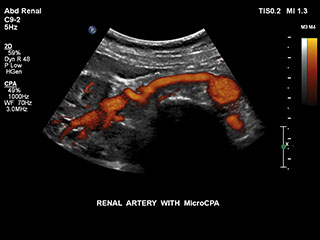

Bisher war die Erfassung von Flussdaten bei kleinen Gefässstrukturen mit niedriger Flussrate schwierig. Die neue EPIQ Funktion MicroCPA bietet eine schnelle und einfache Darstellung von Mikrozirkulation mit niedriger Geschwindigkeit und ermöglicht eine hohe Diagnosesicherheit bei der Beurteilung der Organperfusion oder von kleinen Gefässbetten.